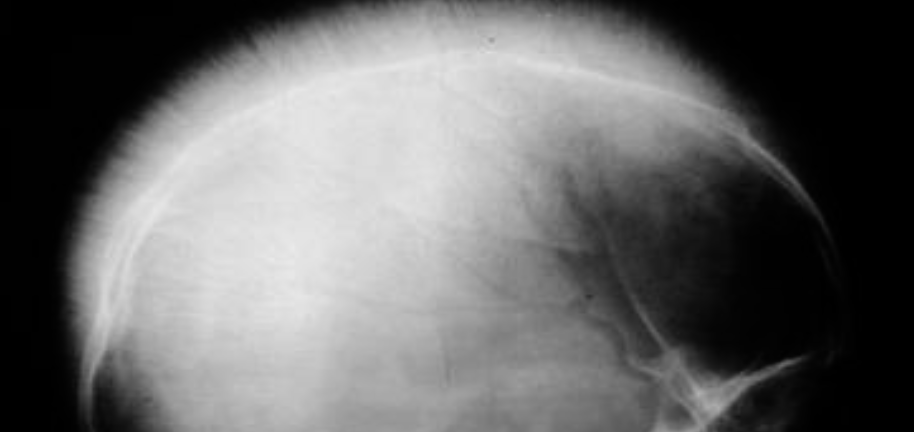

Case 11 Z

-

Describe and explain radiological changes seen in the X-ray?

Hair on end appearance -